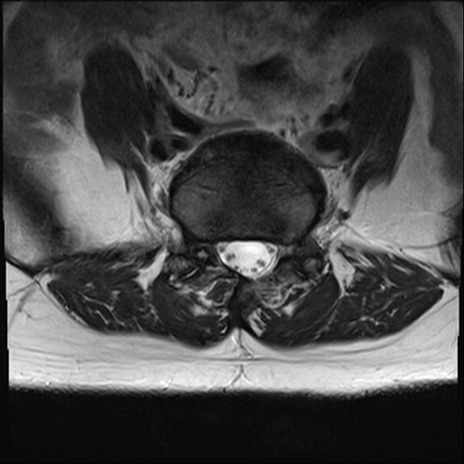

【整形】TIPS症例4 腰椎MRI T2WI(横断像)

腰椎MRI

横断像と矢状断像